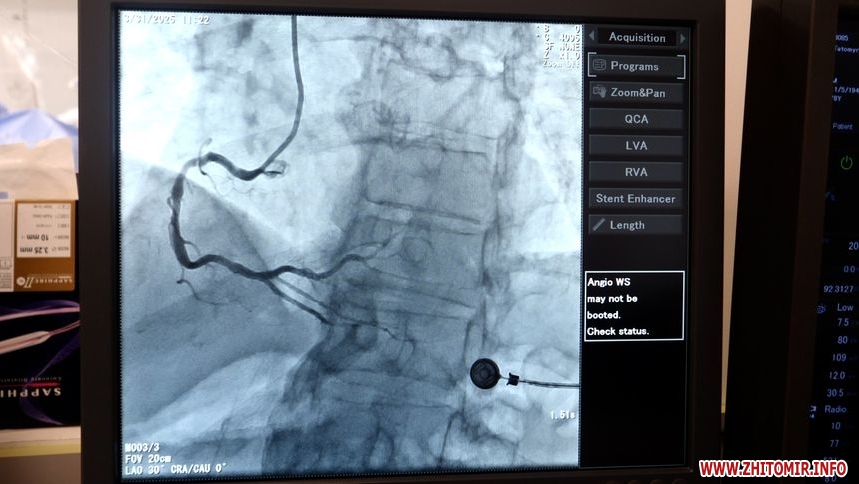

У лікарні працює ангіограф, який придбали у 2021 році, його використовують для діагностики та оперативних втручань. Завідувач кардіологічного центру пояснює, що одного апарату для їх пацієнтів замало.

«Буває, що хворі, які лежать в стаціонарі чекають 7-10 днів, також є хворі, які чекають госпіталізації, це може тривати декілька тижнів. Лікарня має контракти на надання допомоги хворим на мозковий інсульт та інфаркт міокарда, звичайно, це входить у безоплатний пакет, цих хворих ми обслуговуємо абсолютно безоплатно», – розповідає завідувач кардіологічного центру КП «Лікарня №2 ім. В.П. Павлусенка» Житомирської міської ради Олесь Кутній.

12 листопада 2024 року завідувач кардіологічного центру КП «Лікарня №2 ім. В.П. Павлусенка» розповів журналістам Житомир.info, що для пацієнтів в ургентному стані процедури на ангіографі є безоплатними, а запрацювати він має через три місяці.